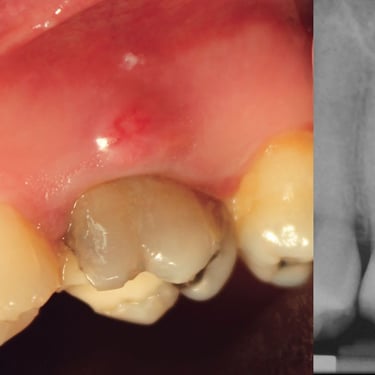

Absceso Periapical Crónico

Un absceso periapical crónico es una infección prolongada en la punta de la raíz del diente que forma una bolsa de pus.

Los pacientes pueden tener dolor leve o no tener síntomas, pero notar una fístula en la encía.

El tratamiento incluye un tratamiento de conducto y, en algunos casos, una cirugía apical. Es crucial tratarlo para evitar la propagación de la infección.